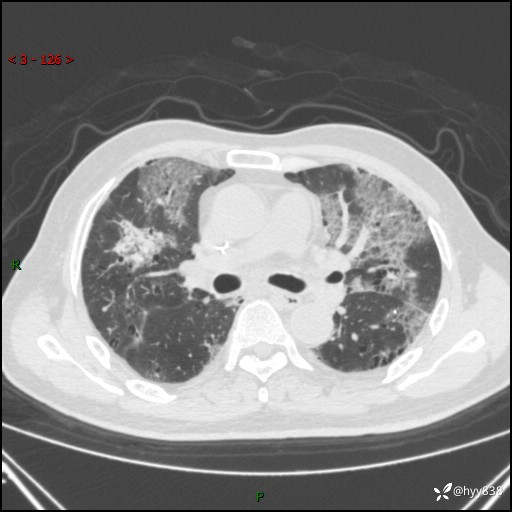

患者性别:男

患者年龄:64岁

简要病史:肝内胆管癌综合治疗后2周余,咳嗽、发热,咳白色泡沫痰。

临床诊断:感染?

讨论:病变性质?